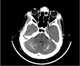

Basal ganglion calcification

Intracranial calcification

Multiple intracranial calcification